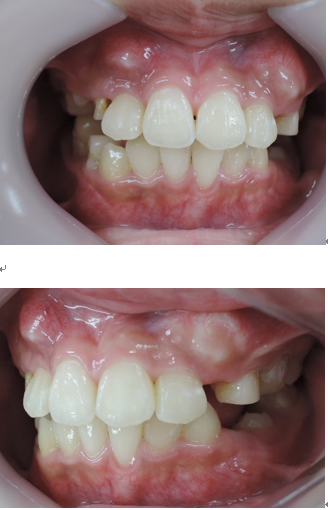

よく診る、難しい症例(奥歯の隙間)

歯列不正

歯を抜かないと治療出来ないと言われた方に。(歯並びが悪い)